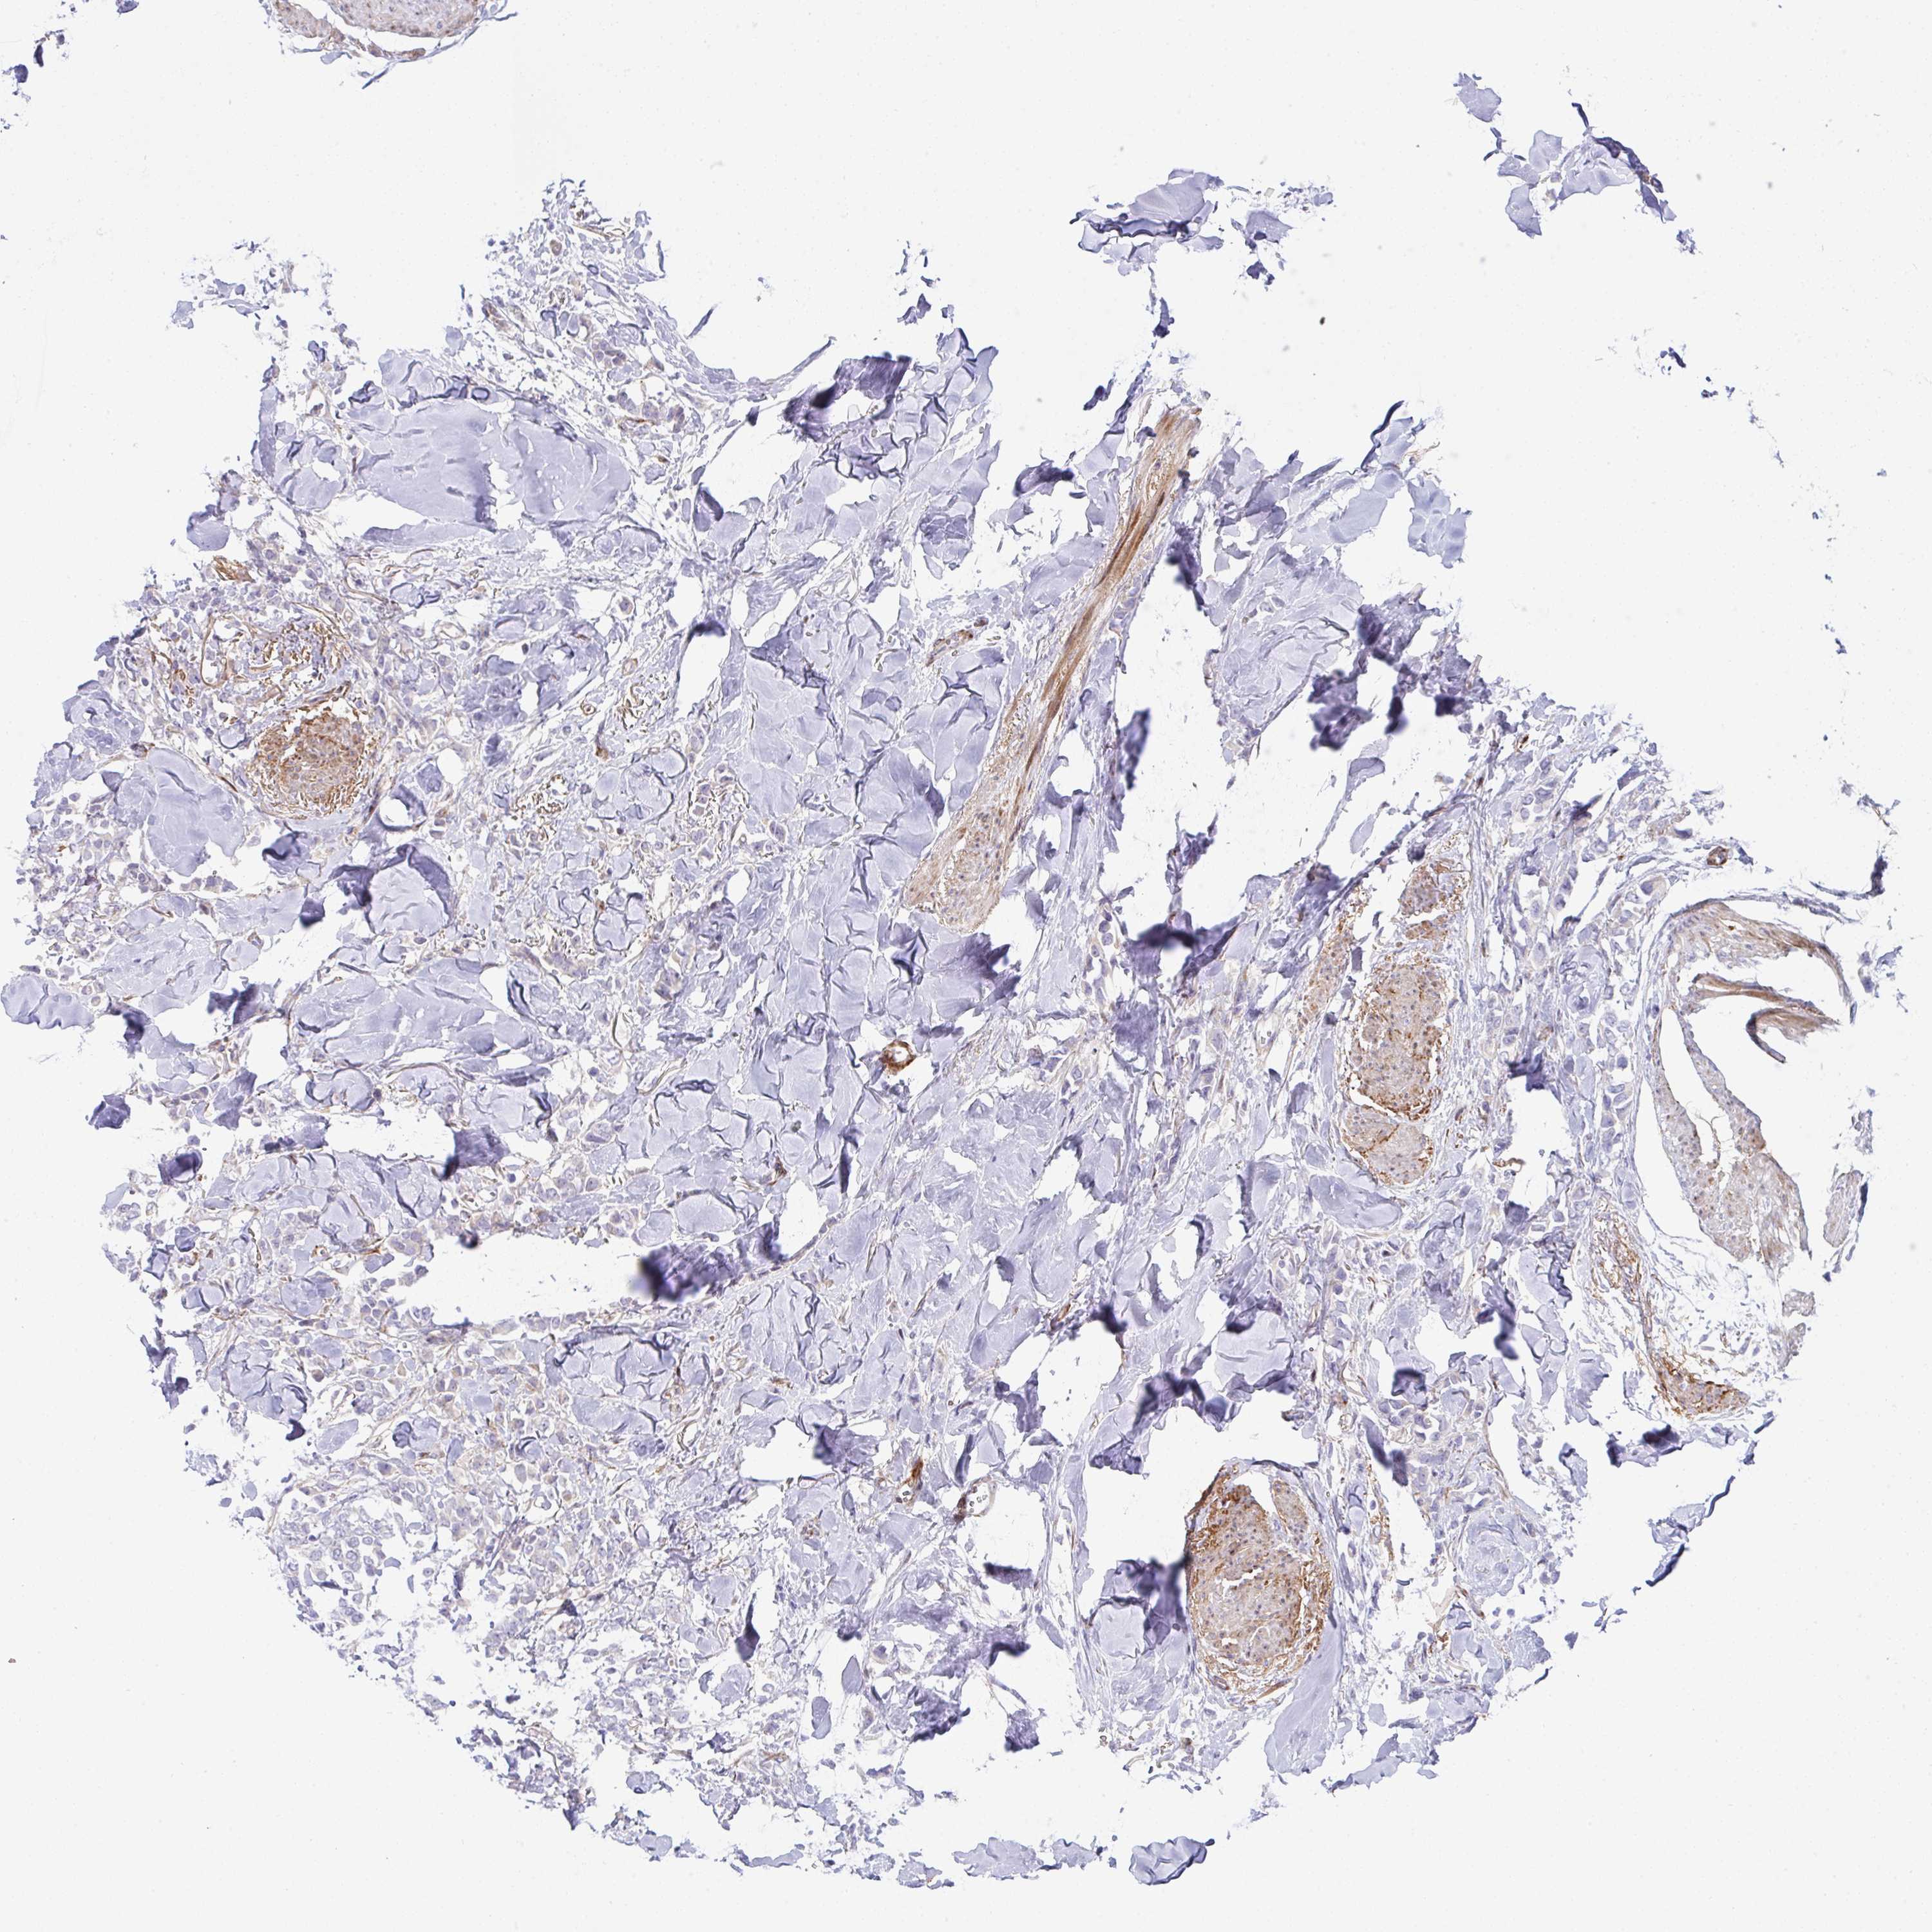

CANCER BREAST CANCER Show tissue menu

BRCA TCGA BRCA VALIDATION PROTEIN EXPRESSION

ANTIBODIES

AND

VALIDATION